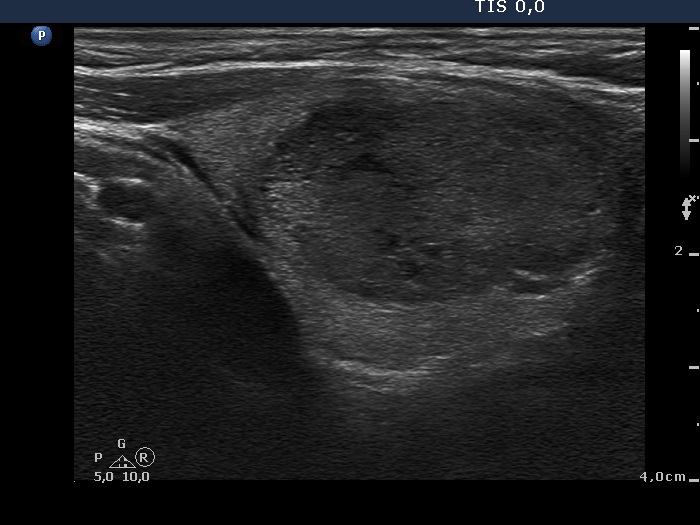

Ultrasonography. The thyroid was minimally hypoechogenic. There was a discrete lesion in the upper part of the right lobe. It was equivocal whether this echo abnormality was a nodule or not. A relatively large hypoechogenic, inhomogeneous nodule was in the lower half of the right lobe. This nodule did not present halo sign, but did a perinodular blood flow.